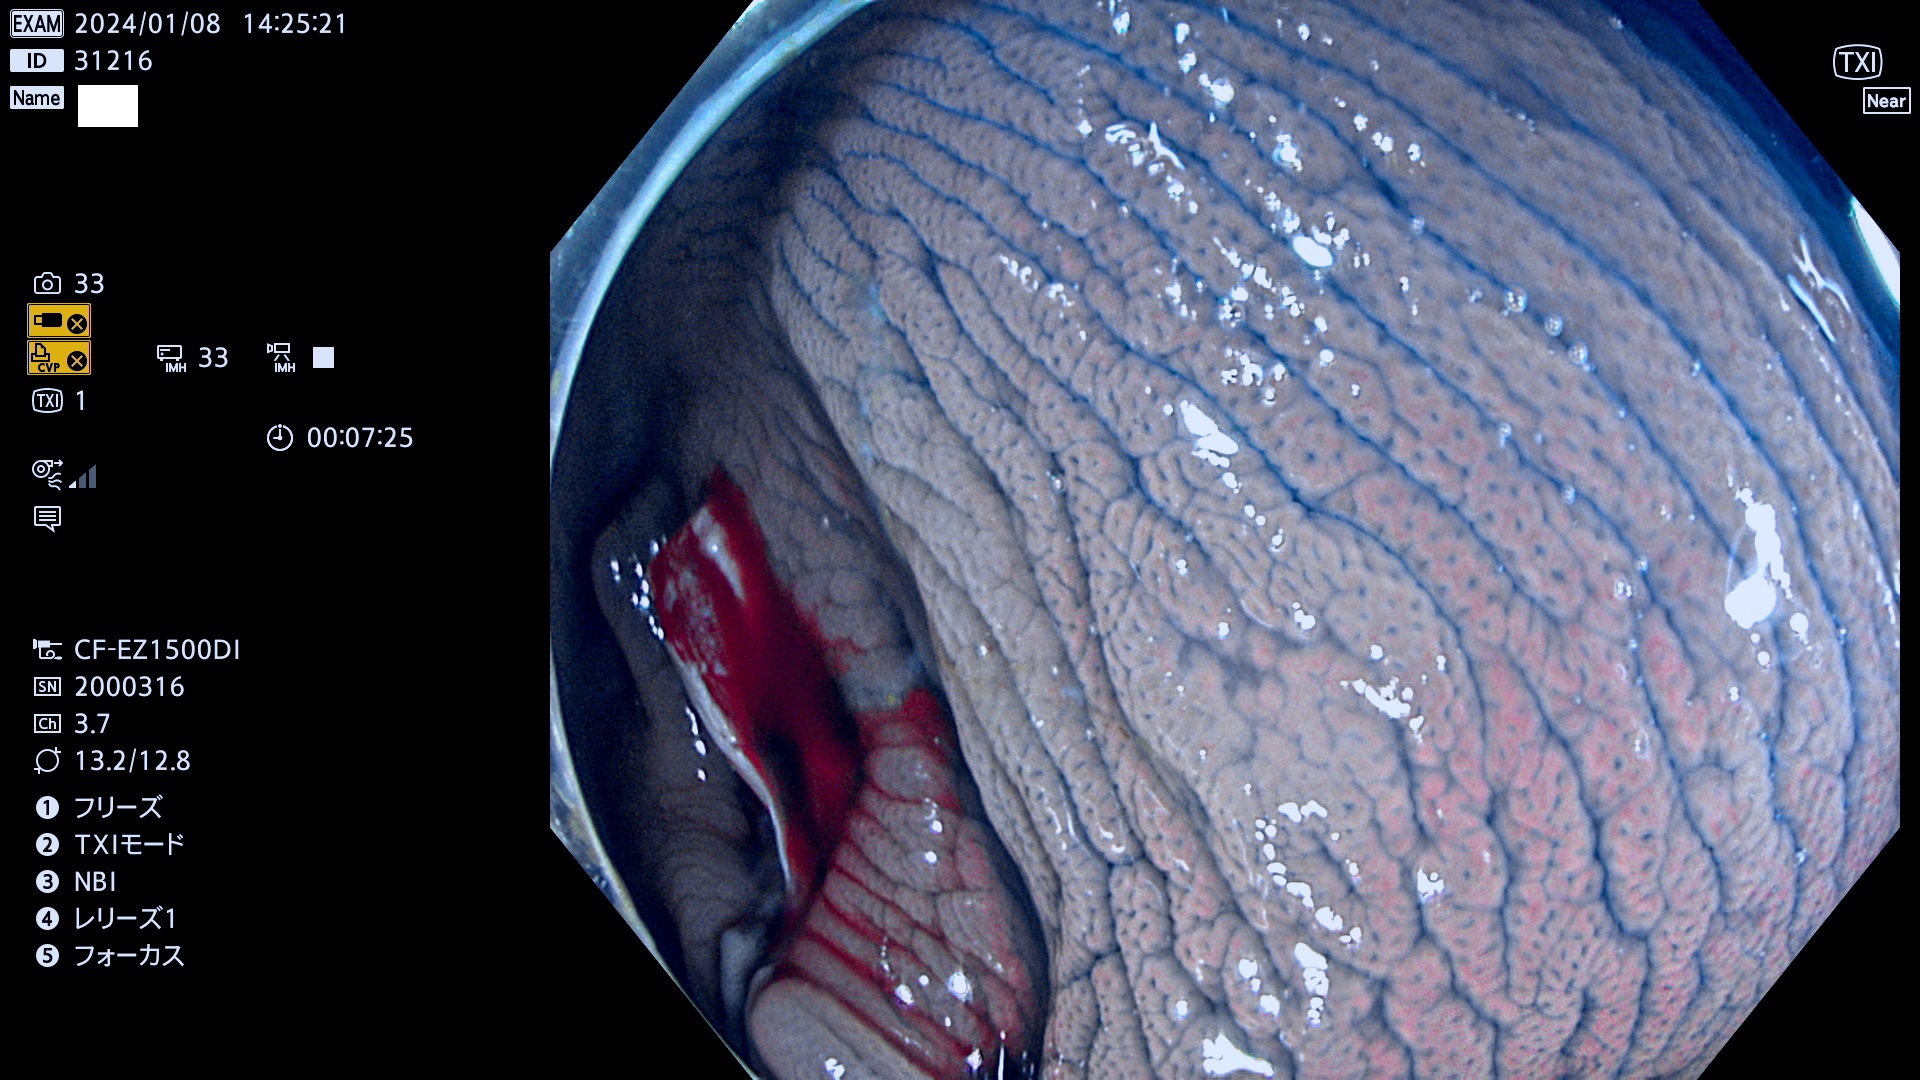

表面型腺腫(Flat Adenoma)の中で、完全に平坦な物をUb、陥凹している物をUcと呼びます。平坦隆起型(Ua)よりも、発見が難しく危険な病変です。

専門的)何故、陥凹していると危険? 癌遺伝子の変異が蓄積すると細胞分裂が盛んになり隆起するのでは?と通常は思われるでしょう。しかし実際は逆です。これは2022年の記事にある「細胞はストレスに直面したら細胞分裂を止める(細胞老化に入り休眠する)という生命の基本的現象」によるものです(Oncogene Stress)。細胞老化を起こすのが癌抑制遺伝子で、この安全装置(ブレーキ)が壊れると癌になります(休眠からの覚醒)。ですから陥凹は「まだ癌では無いが癌化の直前」を意味します。特に「小サイズなのに陥凹している」病変は短期間に腫瘍進化(⇒2021年記事)が起きたことを意味します(=ゲノム不安定性

毎週の検査(木・金・土・日)に発見されたUb、Uc型・腺腫を、その週の日曜の夜にUPし1週間、提示します。

抽出の対象期間 2024年1月6日(土)〜1月8(月)の4日間(34件の検査)7件